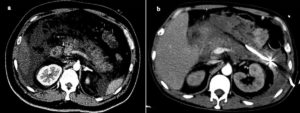

Для дифференциальной диагностики кист, опухолей, воспалений проводят КТ почек с контрастным веществом.

Дифференцирование таких образований основано на свойстве злокачественных образований накапливать рентгеноконтрастной препарат, при этом плотность опухоли возрастает более чем на 5-15 единиц по шкале Хаунсфилда.

Основными признаками доброкачественных кист на КТ являются круглая форма образования с гладкой стенкой, четкими контурами, а также однородное содержимое плотностью менее 20 единиц.

Исключением являются гиперденсивные кисты, плотность которых может быть более 20 единиц из-за содержания в них большого количества белка либо геморрагических компонентов. Также КТ-признаками кист является наличие в образовании узелковых уплотнений стенки, внутренних перегородок и многокамерности.

После введения контрастного вещества плотность, форма и величина простой кисты не изменяется, при этом плотность паренхимы почки возрастает.

В современной практике основным методом верифицирования кальцинатов является КТ. Присутствие кальцинатов в кисте может свидетельствовать о возможном озлокачествлевании процесса. Однако мелкие кальцинаты линейной формы могут встречаться в перегородке либо стенке доброкачественных кист.

Например, при ангиомиолипоме фото КТ без усиления показывает участки жировой ткани с пониженной плотностью.